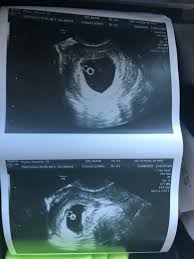

6 Weeks 4 Days Pregnant Ultrasound Twins : Transvaginal Ultrasound At 5 Weeks And 6 Days Of Gestation Download Scientific Diagram - Any, even the smallest one, amount of bleeding in it or pink spotting, should put on her guard.. We are first time parents and this is our first ultrasound. I actually told my doctor that all i wanted her to tell me from the ultrasound was that i wasn't having twins. Surprise twins at 20 weeks. Once around 6 weeks, once after a vaginal ultrasound exam at 16 weeks, and once last at 30 weeks. Between 5 ½ to 6 ½ weeks, a fetal pole or even a fetal heartbeat may be detected by vaginal ultrasound.

They said the baby looked small and measured about 6 weeks. This was taken at 4 weeks 6 days. Your first pregnancy ultrasound is usually an exciting event: Jetzt timeblock® ganz einfach bei douglas bestellen und 2 gratisproben sichern! Transvaginal ultrasound, by contrast, can detect pregnancies earlier, at approximately 4 ½ to 5 weeks gestation.

What are the chances of having twins? When six full weeks have passed (after week 6+0) you should be able to detect all kinds of twins using ultrasound. A full bladder provides an ultrasonic window to better see what's inside the uterus. I've been posting in october 2012 since i found out i was pregnant in february. 6 weeks 4 days pregnant progress check in the 7th week of pregnancy, your baby's lungs are starting to develop. They confirmed the presence of a gestational sac, yolk sac and fetal dipole, but could not detect a heartbeat. Between 5 ½ to 6 ½ weeks, a fetal pole or even a fetal heartbeat may be detected by vaginal ultrasound. The fetal pole is the first visible sign of a developing embryo.

They confirmed the presence of a gestational sac, yolk sac and fetal dipole, but could not detect a heartbeat.

We had the wonderful opportunity to see our baby's heart flickering on the screen!!! They said the doctor will call me and they may book an ultrasound in another two weeks. By four weeks, twins will start showing during ultrasound in form of 2 gestational sacs, but you cannot get clear indication of twins until 6 weeks. The ultrasound image is of twins at 4 weeks. No fetal heartbeat detectable at 5 weeks 6 days ultrasound.